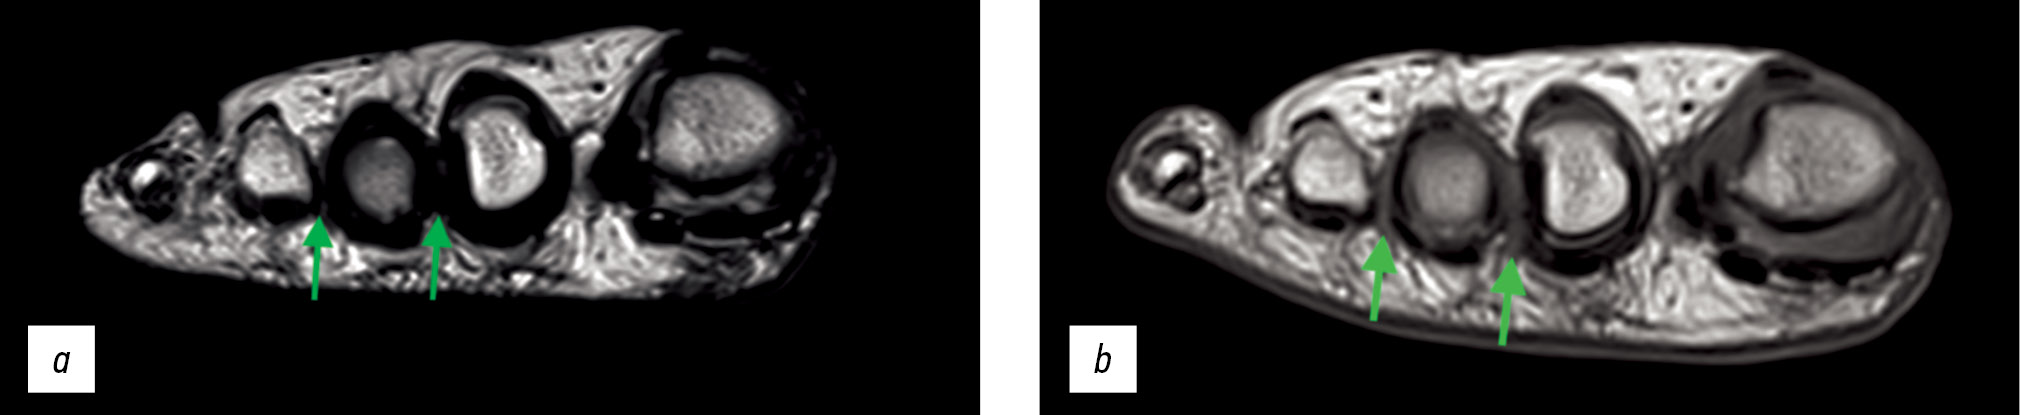

В 2020 году пациентке было выполнено УЗИ, на котором выявлены рубцовые изменения во втором межпальцевом промежутке, невринома культи нерва, неврома Мортона в третьем межпальцевом промежутке. Пациентка проходила консервативное лечение: блокады с гидрокортизоном с временным положительным эффектом (не более недели). Учитывая хронический болевой синдром, врачом-неврологом была назначена системная терапия габапентином — без положительного эффекта. На исследовании методом магнитно-резонансной томографии (МРТ) в сентябре 2020 года (рис. 1a) выявлены два гипоинтенсивных образования во втором и третьем межпальцевых промежутках. В декабре 2020 года пациентке выполнена радиочастотная термодеструкция постхирургической культи нерва и кожного нерва правой стопы во втором межпальцевом промежутке с временным (не более двух недель) положительным эффектом. Для уточнения диагноза и определения тактики дальнейшего лечения пациентка повторно выполнила УЗИ правой стопы (медицинская документация предоставлена). Были выявлены УЗ-признаки гипоэхогенного образования в третьем межплюсневом промежутке, признаки постоперационных изменений во втором межплюсневом промежутке, признаков асимметрии строения подошвенных нервов между правой и левой нижними конечностями не обнаружено.

В марте 2021 года пациентке было выполнено введение в поражённые межплюсневые промежутки препарата ксеомин 50 ед с умеренным положительным эффектом. В декабре 2021 года пациентке осуществлена радиочастотная ризотомия культи нерва и кожного нерва правой стопы во втором и третьем межпальцевых промежутках без положительного эффекта. В качестве консервативной терапии для облегчения болей пациентка принимала лирику (прегабалин) 150 мг с умеренным положительным эффектом. На МРТ-исследовании (рис. 1b) отмечена слабоположительная динамика — уменьшение плотности рубцовой ткани во втором межпальцевом промежутке.

Рис. 1. Этапные магнитно-резонансные томографии МРТ пациентки С.: a — сентябрь 2020 г.: два гипоинтенсивных образования во втором и третьем межпальцевых промежутках; b — сентябрь 2021 г.: два гипоинтенсивных образования во втором и третьем межпальцевых промежутках. При сравнении с МРТ от 2020 года — увеличение интенсивности сигнала (уменьшение плотности фиброза).

Fig. 1. Staged magnetic resonance imaging MRI of patient S.: a — september 2020: two hypointensive lesion in the second and third interdigital spaces; b — september 2021: two hypointensive lesion in the second and third interdigital spaces. When compared with MRI from 2020, an increase in signal intensity (decrease fibrosis density).